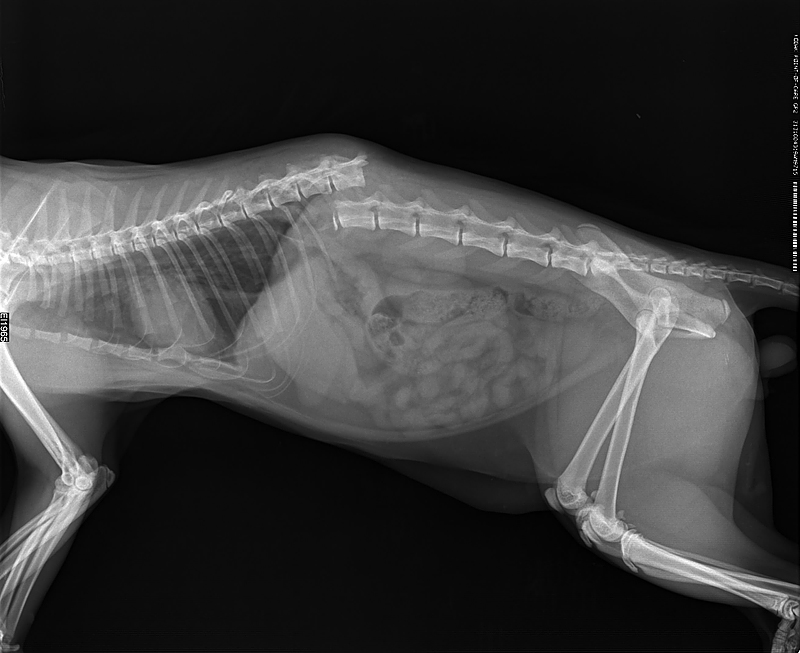

Рентген Задней Лапы Кошки: Нормы и Диагностика